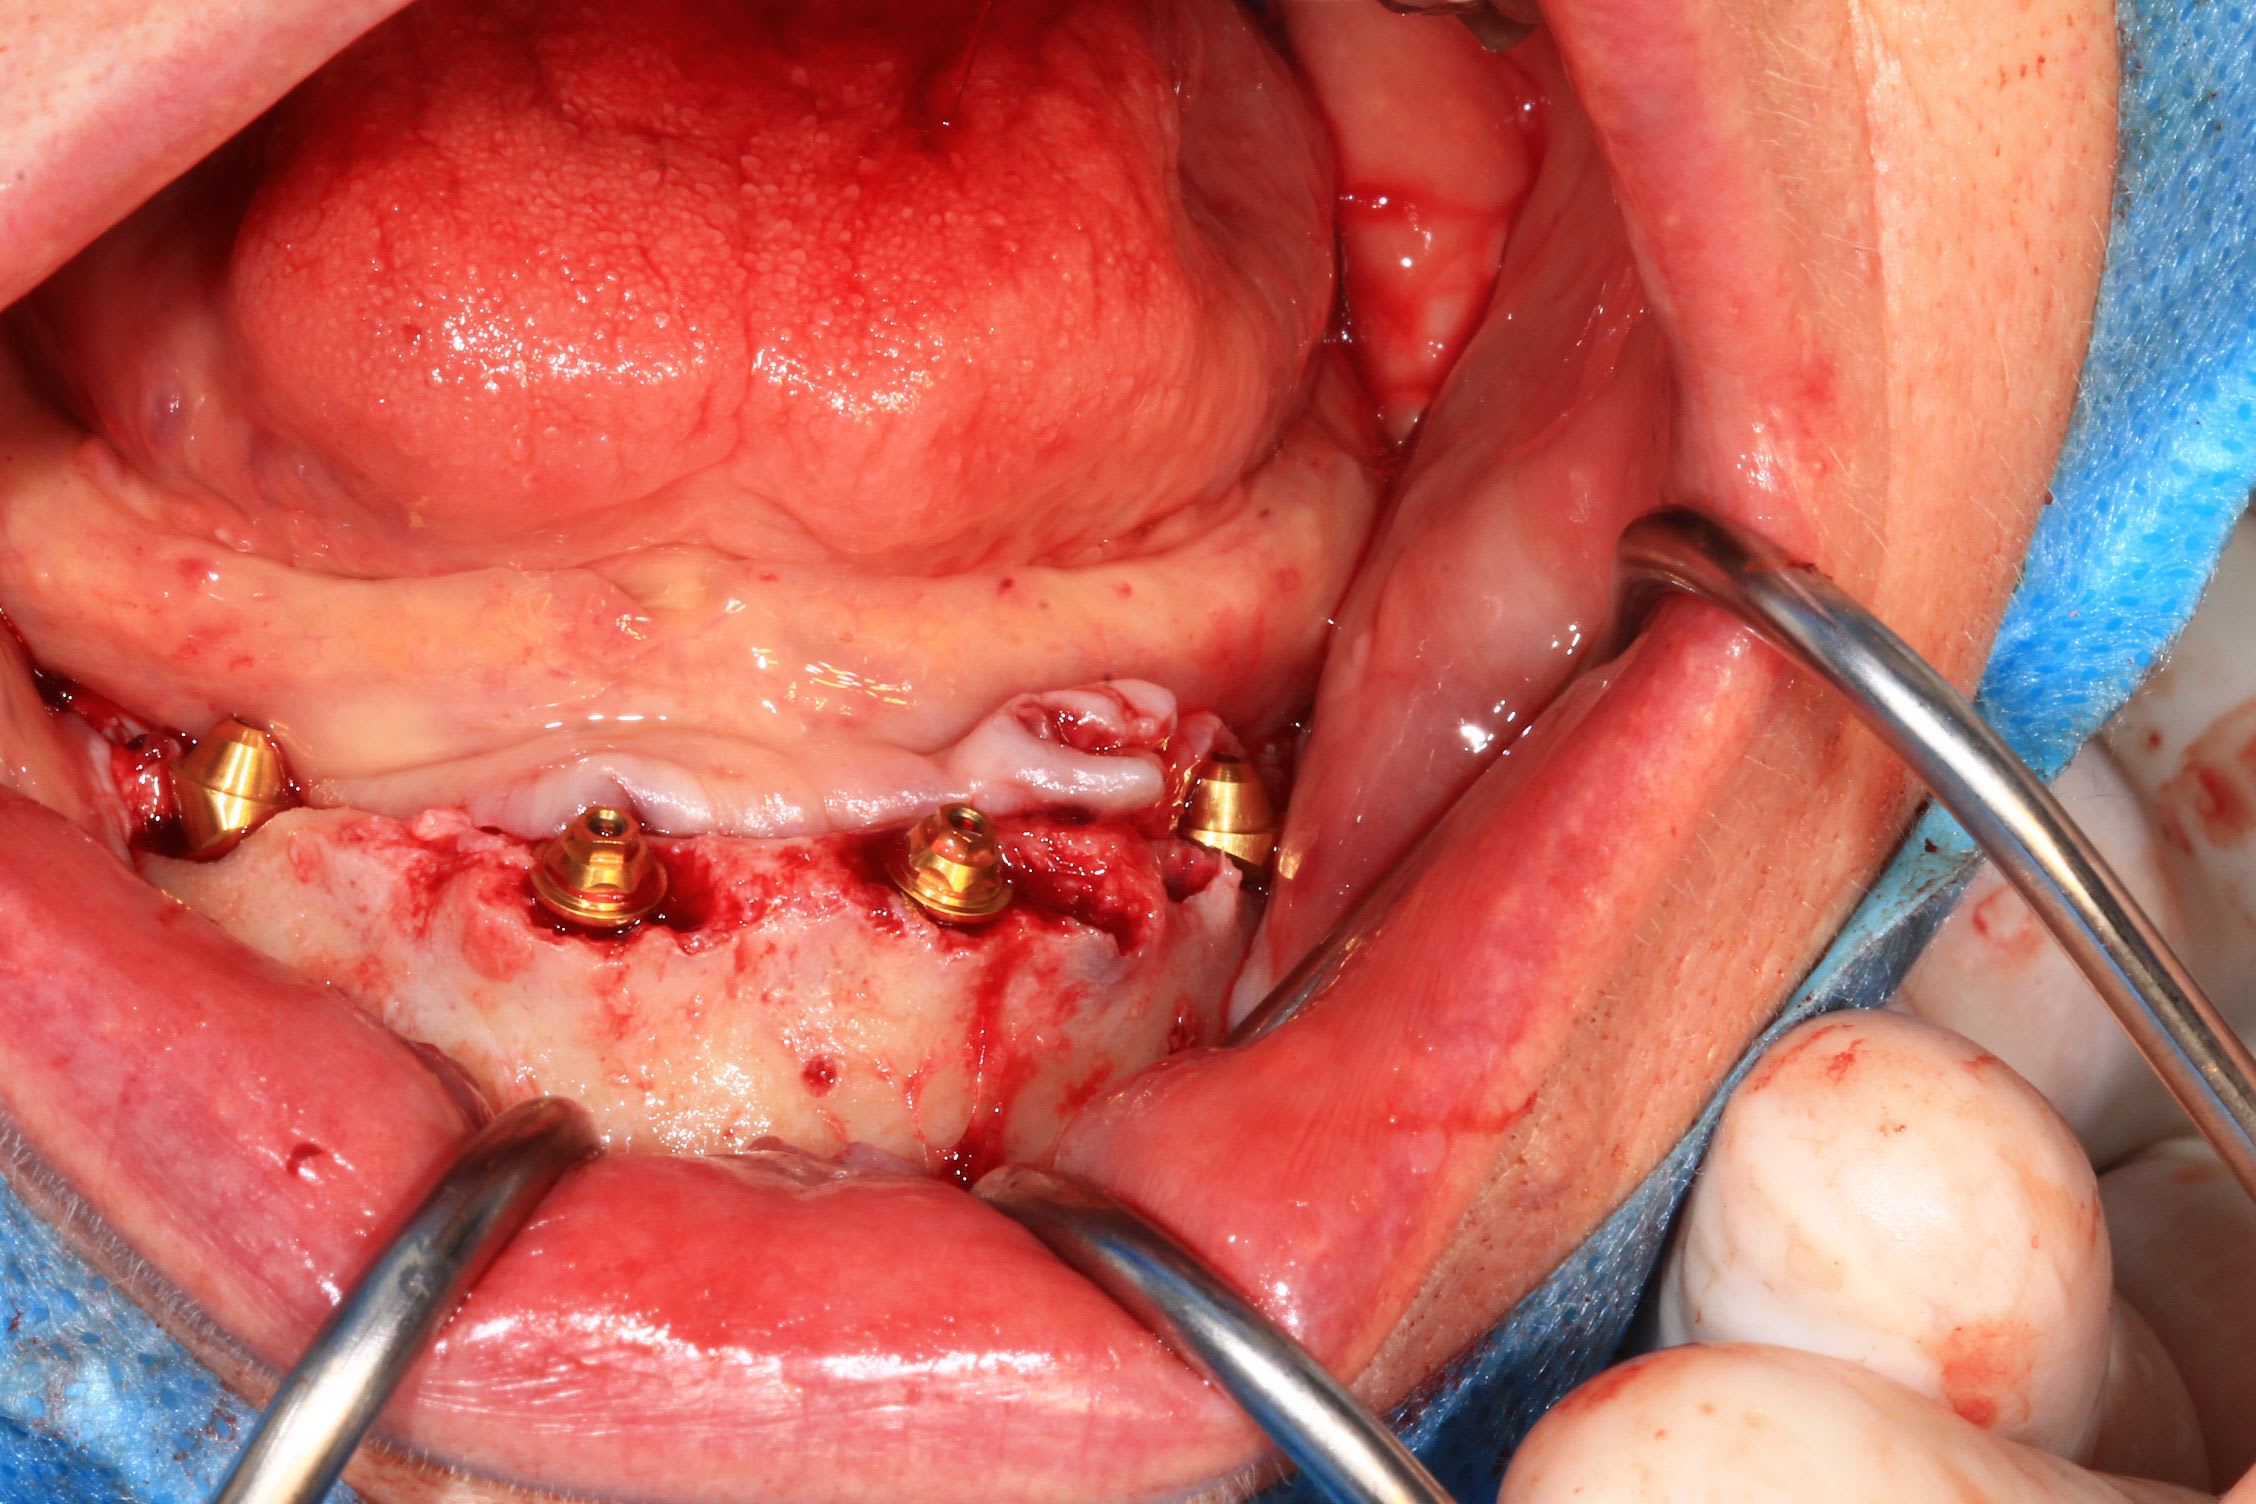

Suture en matelassier horizontal sous le bridge + vertical sur le bridge : gain de gencive kératinisée .

Bridge imprimé au cab , résine flexera .

Vis rosenscrew.